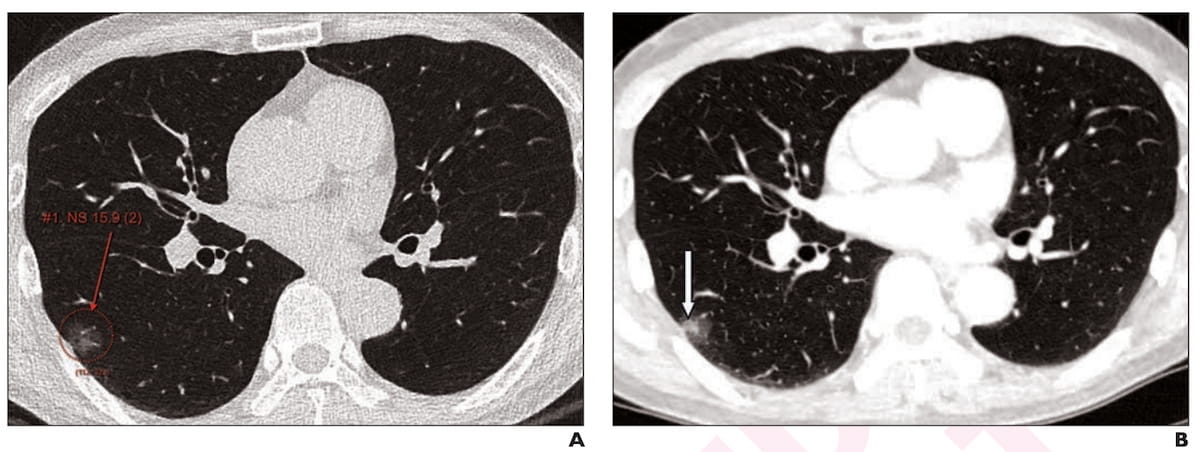

Here one can see axial low-dose CT imaging revealing a 16 mm subsolid nodule at initial screening (A) and subsequent growth of the solid component of the nodule at two years (B) in a 65-year-old male patient. The nodule was detected by standalone AI, adjunctive use of AI and unassisted radiologist assessment. (Images courtesy of the American Journal of Roentgenology.)